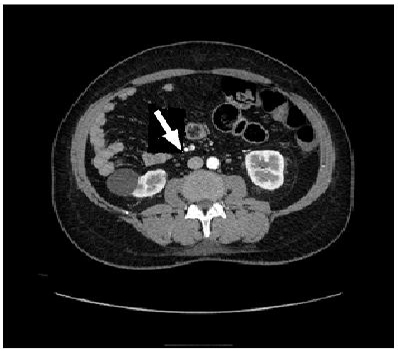

A 50-year-old female without any significant past medical or surgical history presented to the emergency room after being involved in a pedestrian versus automobile accident. The physical exam was unremarkable. CT scans of her abdomen revealed that the cecum and ascending colon (Figure 1, arrow) were located predominately on the left side. Also, the superior mesenteric vein and the superior mesenteric artery were inverted in respect to their normal anatomic relationship with the superior mesenteric vein being located to the left of the superior mesenteric artery instead of to the right as in their normal anatomic configuration (Figure 2, arrow) which is a diagnostic of congenital malrotation. She was discharged after 24-hour observation and remained asymptomatic.

Figure 2: Figure 2: Abdominal CT scan demonstrating the inversion of the superior mesenteric artery and superior mesenteric vein.